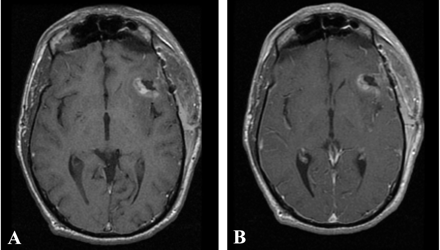

Both patients underwent IMRI-guided resection of their tumors. Preoperative MR imaging demonstrated the targeted lesion. Intraoperative MR without gadolinium, following the prior administration of ferumoxtran-10, easily provided images that demonstrated the lesions seen on preoperative MR images obtained in both patient 1 (Fig 1) and patient 2 (Fig 2). In one operation, post-resection imaging revealed a persistently enhancing area that was then resected (Fig 3). Even in the low-field-strength IMRI system, ferumoxtran-10 provided adequate imaging of the lesions in both of these patients. Postoperative MR images obtained in both patients had no significant enhancement with gadolinium, which suggests resection of the enhancing tumor bulk (Figs 4 and 5). Both postoperative MRIs show high T1 signal intensity in the wall of the resection cavity. The walls of the cavities, however, do not appear to enhance significantly with gadolinium. Figure 5 also shows the resection cavity itself filled with T1 hyperintense material. The cause of this residual T1 hyperintensity, either from blood or ferumoxtran, is unclear. Iron staining of one patient’s lesion demonstrated iron accumulation within peritumoral reactive cells (Fig 6).

Postoperative T1-weighted MR imaging from patient 1 performed 72 hours after surgery, without (A) and with (B) gadolinium. No residual areas of significant gadolinium enhancement are seen.